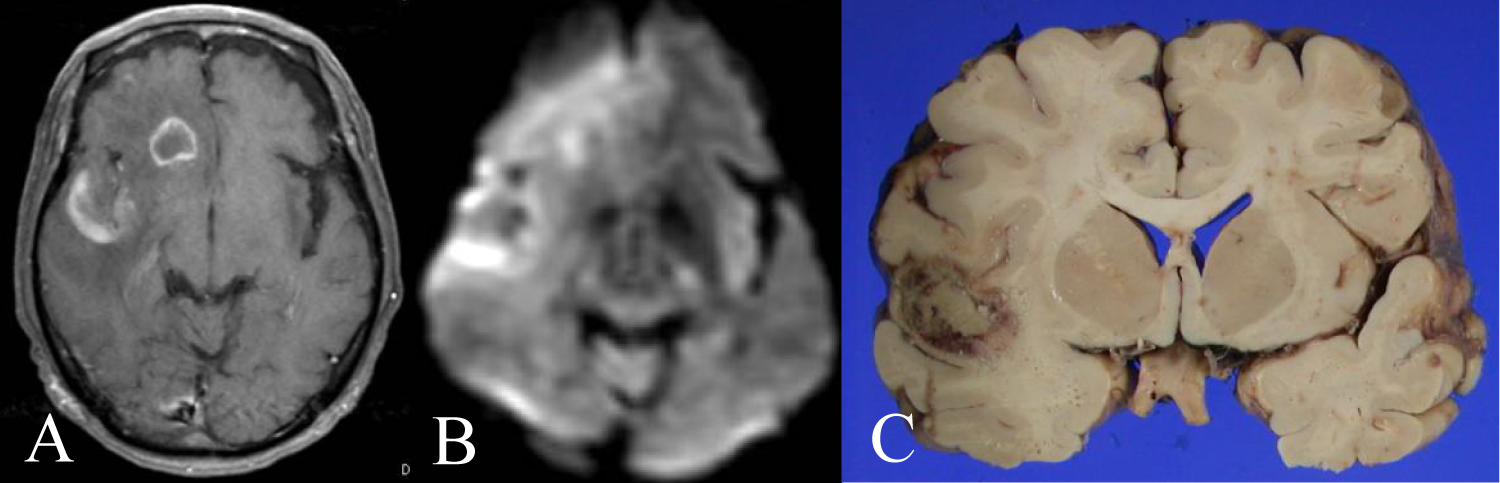

52-year-old man presented fever and dullness, and other doctor diagnosed his AIDS. The doctor introduced combined ART to him. His character changed 7 months later and came to our office. His head MRI showed a ring enhancement at right frontal lobe (Figure 5A). FDG-PET showed a ring like high uptake and central low uptake at same lesion (Figure 5B). Histopathological findings were DLBCL. Although we performed rituximab and radiotherapy to him, he died at 12 months (Figure 5C).

Figure 5: A 52 year-old man presented his character changed. A) His head MRI showed a ring enhancement at right frontal lobe; B) FDG-PET showed ring like high uptake and central low uptake at same lesion; C) DWI showed slight ring like high intensity. View Figure 5